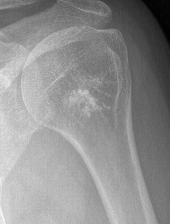

X-ray

Intralesional calcification - punctate, stippled calcification and broken rings

Differential diagnosis long bone with intralesional calcification

1. Enchondroma

2. Bone infarct

3. Chondrosarcoma